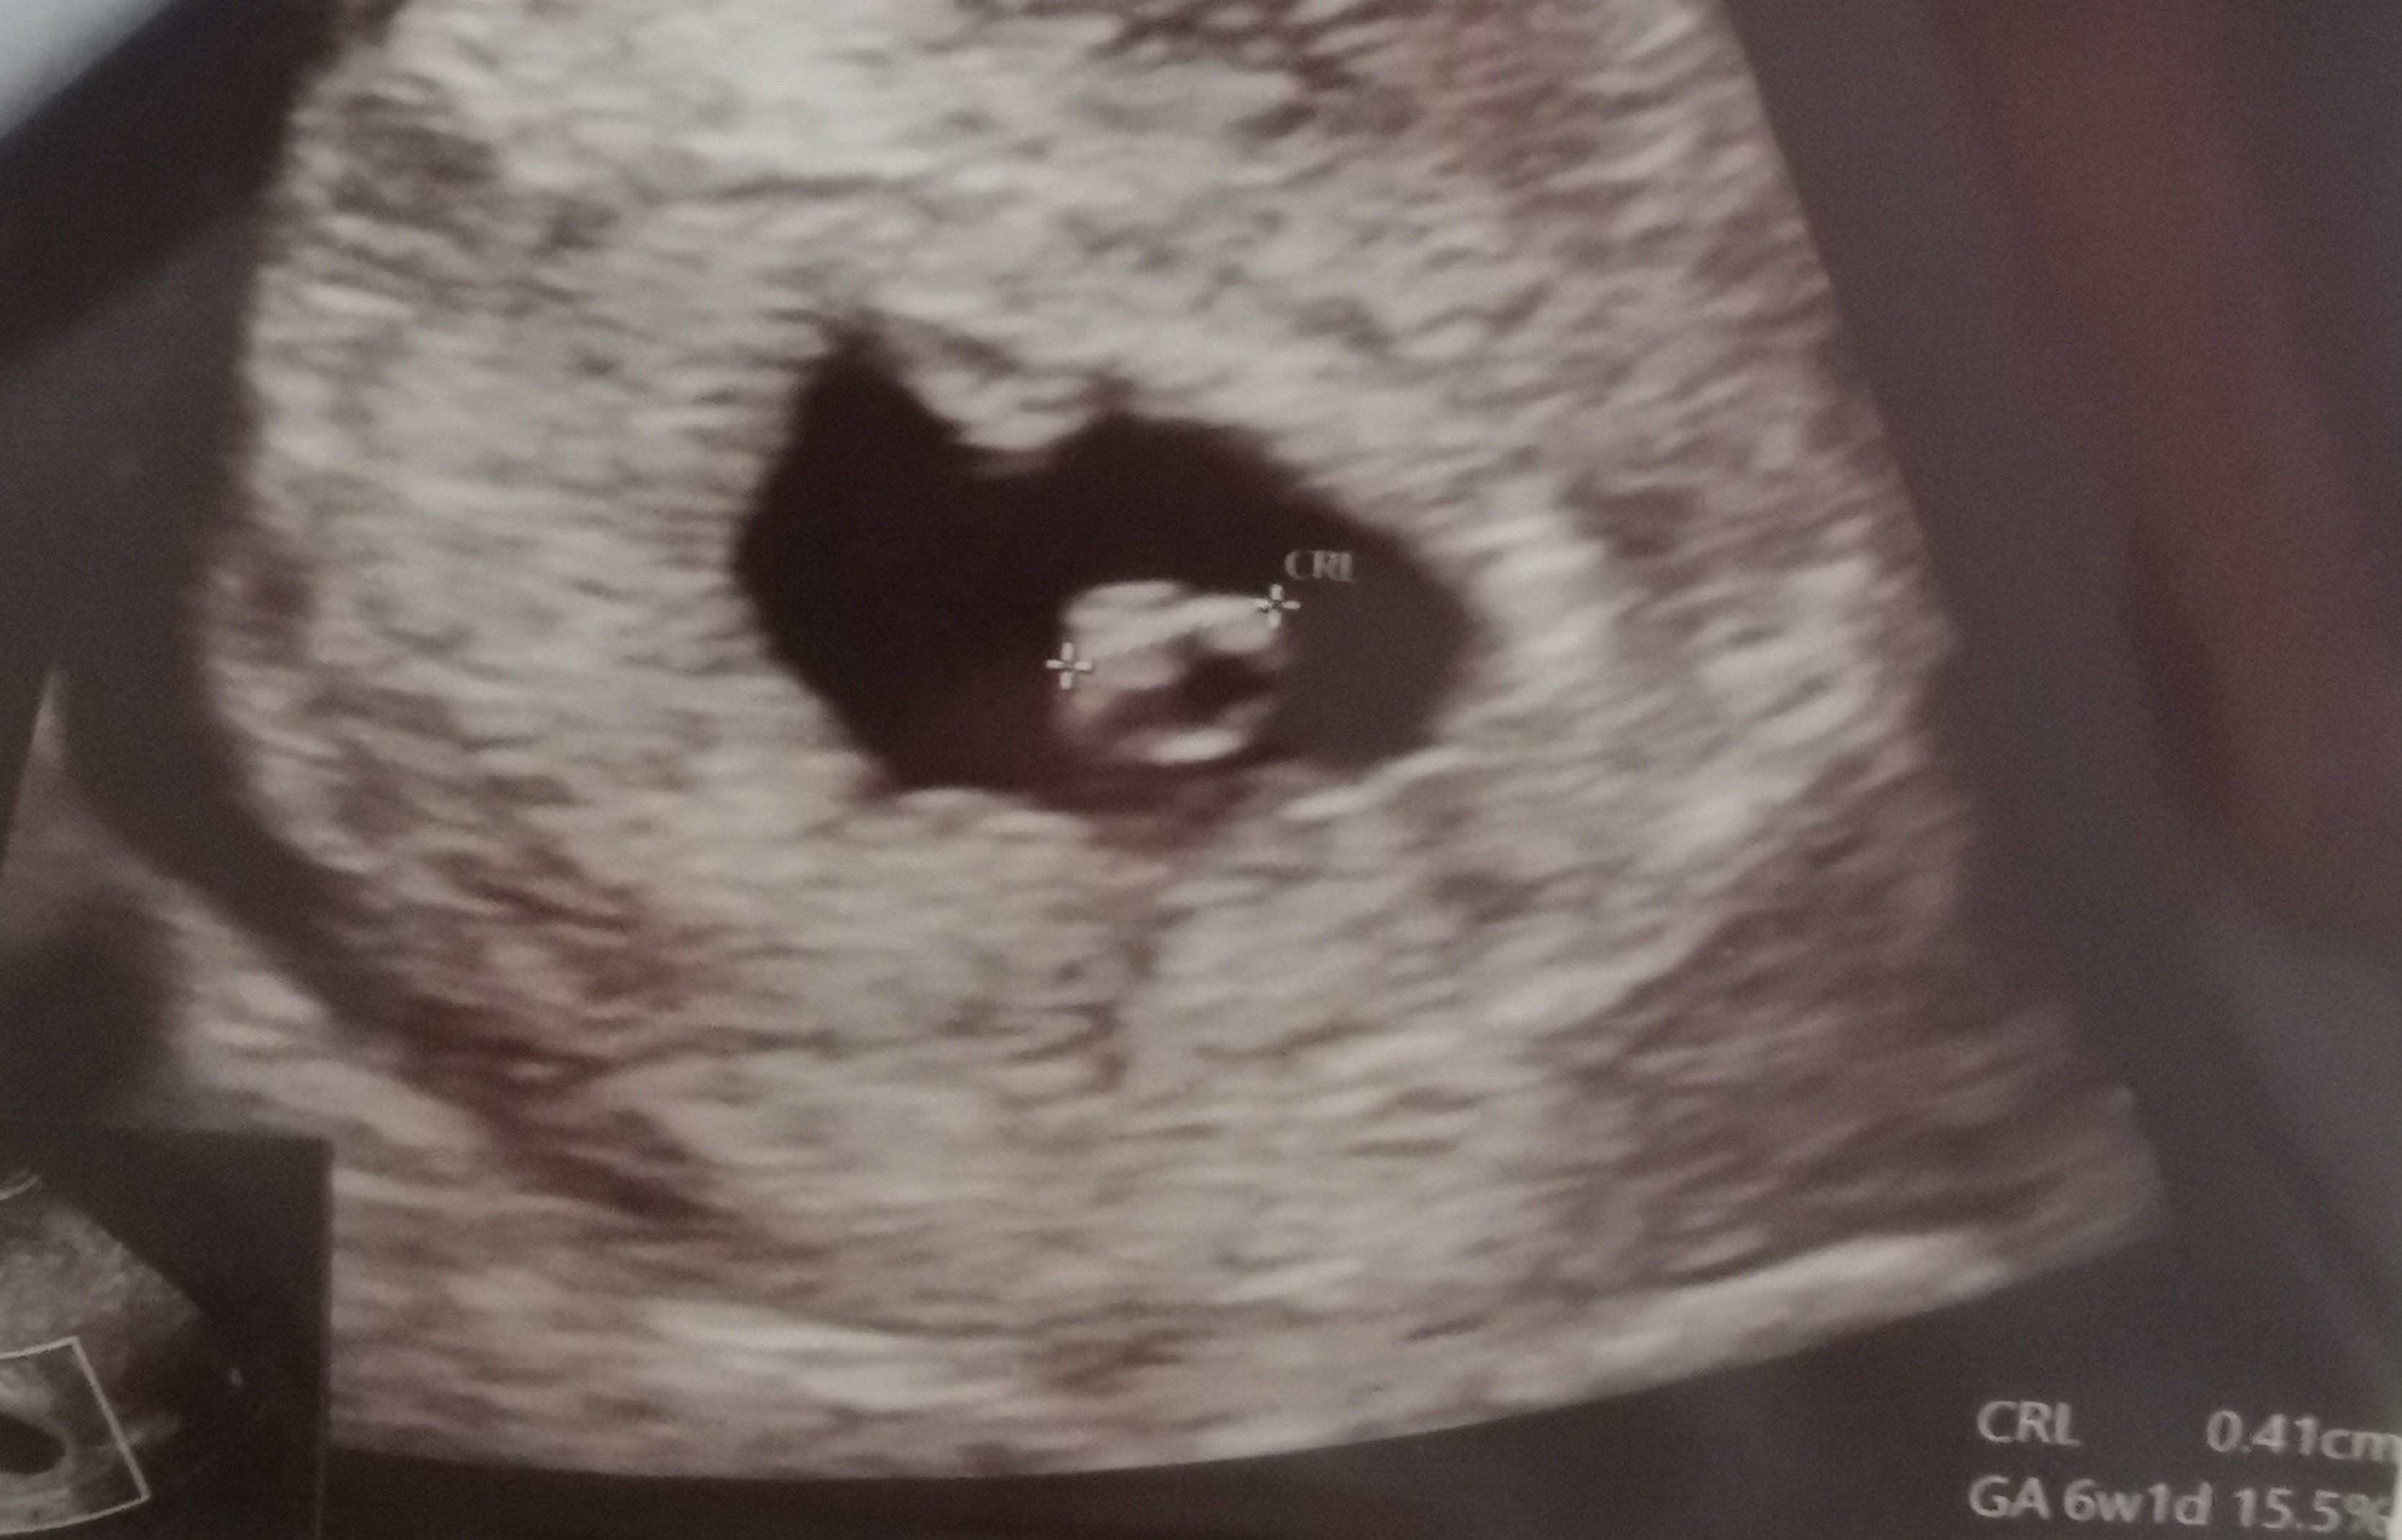

O matko, wszystko dobrze ...tylko Pan Doktor nas poinformował, że mamy 2 serduszka 😱. Będą bliźniaki. Tego się kompletnie nie spodziewaliśmy ... Jeszcze chyba nie oswoiłam się z tą myślą ....za 2 tygodnie muszę umówić wizytę bo nie wiadomo czy każdy bobas ma swoje łożysko, czy mają jedno wspólne ... trochę się denerwuję ... ale też cieszę ... jakoś to bedzie😊❤️❤️

Już po wizycie. Ogólnie wszystko w porządku, serduszko mocno bije, widoczne były delikatne ruchy, co ma potwierdzać, że układ nerwowy też dobrze się rozwija.

CRL 2,41 cm.

Jednak martwi trochę wiek ciąży z USG bo różni się od tego z OM, wskazuje na młodszą o 3-4 dni. O ile normalnie to się często zdarza i nie jest powodem to niepokoju, to my jesteśmy po in vitro i teoretycznie wiemy dokładnie jaki był wiek zarodka i kiedy był transfer...

Lekarz jednak kazał się nie martwić bo te pomiary nie zawsze są idealne, ale wiadomo jak jest, z tyłu głowy siedzi już niepewność, tym bardziej że to moja pierwsza ciąża.